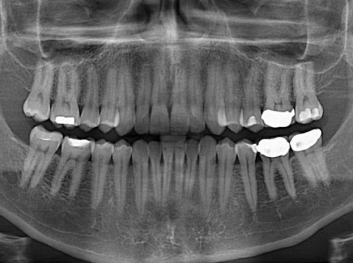

哈佛大學(xué):新型生物材料讓牙齒再生 來源: 南京泰盛生物科技有限公司 發(fā)布時(shí)間:2018-04-10

損壞的牙齒如何自我修復(fù)?近日,來自哈佛大學(xué)和諾丁漢大學(xué)的研究人員研發(fā)了能夠刺激牙齒干細(xì)胞再生的新型生物材料,而這種新材料研發(fā)成功的背后,正源于他們對(duì)牙齒如何實(shí)現(xiàn)自我修復(fù)這個(gè)課題的不斷探索。

據(jù)美國期刊《大眾科學(xué)(Popular Science)》報(bào)道,此種新型生物材料,不僅可以有效地取代傳統(tǒng)補(bǔ)牙填充物,刺激牙齒干細(xì)胞再生,患者也有望無需再接受根管治療,使蛀牙患者免除牙根感染或牙髓壞死的苦惱,一個(gè)全新的牙齒治療時(shí)代即將來臨。

Adam Celiz,是來自諾丁漢大學(xué)的研究人員,他和同事開發(fā)的這種新型合成生物材料,能刺激干細(xì)胞在牙髓部的生長。與普通材料一樣,這種合成材料被填充到牙齒并用UV光硬化。

在體外測(cè)試中,材料刺激干細(xì)胞進(jìn)入牙本質(zhì)的增殖和分化速度,促進(jìn)形成牙齒骨組織。研究人員認(rèn)為,一旦材料在受損牙齒中應(yīng)用,這些干細(xì)胞可以自動(dòng)修復(fù)來自填充物上的損壞。在本質(zhì)上,該生物材料將使牙齒自愈。

在未來,Adam Celiz說,可再生材料能制成各種填充物以便受損牙齒的自身治愈,降低補(bǔ)牙失敗率,甚至?xí)蟛糠秩藢?duì)根管治療的需要。